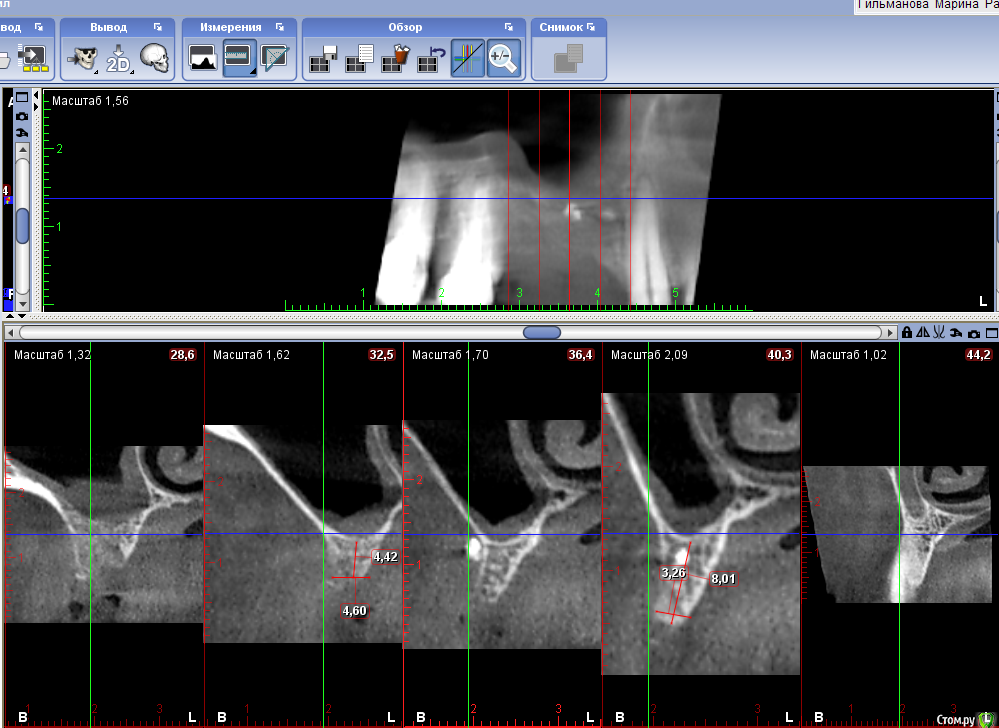

Sergiosse Опубликовано 14 января, 2019 Поделиться Опубликовано 14 января, 2019 (изменено) Коллеги Добрый вечер.Два вопроса. Как думаете пройдет здесь установка имплантов одномоментно с ОСЛ И расщеплением . А как вы сделали вы? Изменено 14 января, 2019 пользователем Sergiosse Ссылка на комментарий